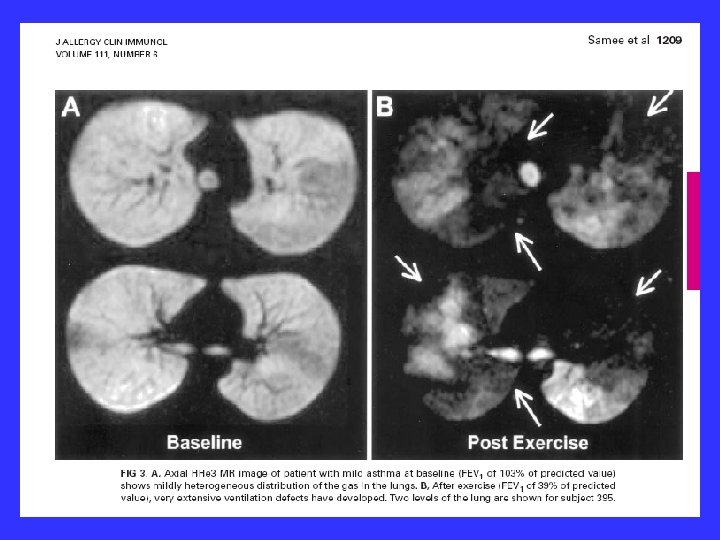

He 3 MR showing ventilation defects in a normal subject and in increasingly severe asthmatics. Author Samee, S ; Altes T ; Powers P ; de Lange EE ; Knight-Scott J ; Rakes G Title Imaging the lungs in asthmatic patients by using hyperpolarized helium-3 magnetic resonance: assessment of response to methacholine and exercise challenge Journal Title Journal of Allergy & Clinical Immunology Volume 111 Issue 6 Date 2003 Pages: 1205 -11